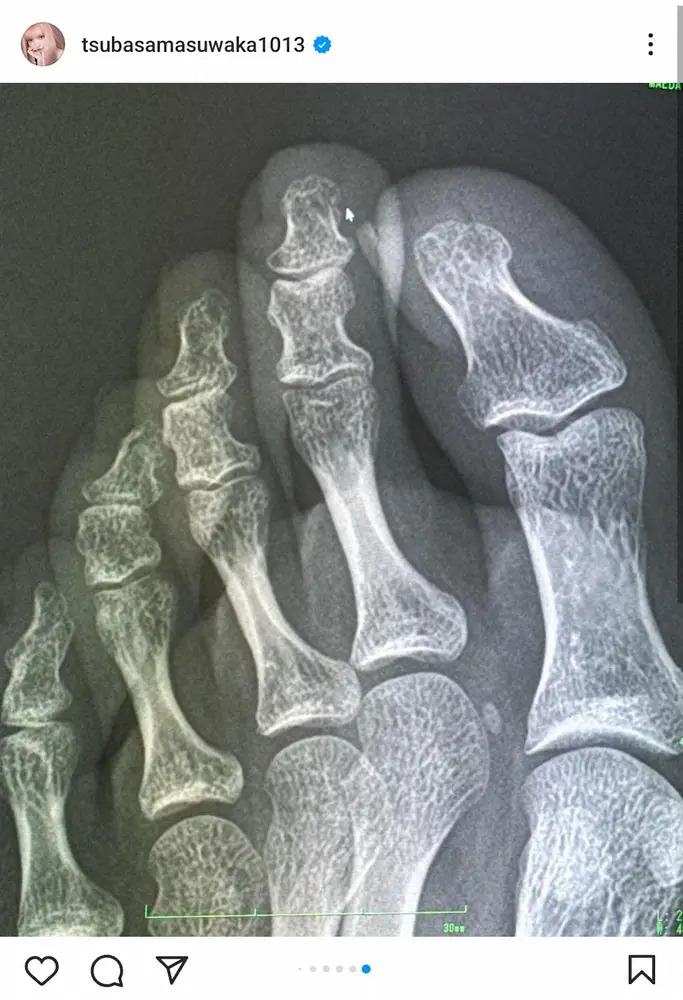

益若つばさのインスタグラム(@tsubasamasuwaka1013)より 益若つばさ 「また骨折れたのか」左足中指にシャンプーボトル落下で「と… ギャラリーで見る この記事のフォト 2024年05月21日の画像一覧 もっと見る 2024年05月21日の画像をもっと見る